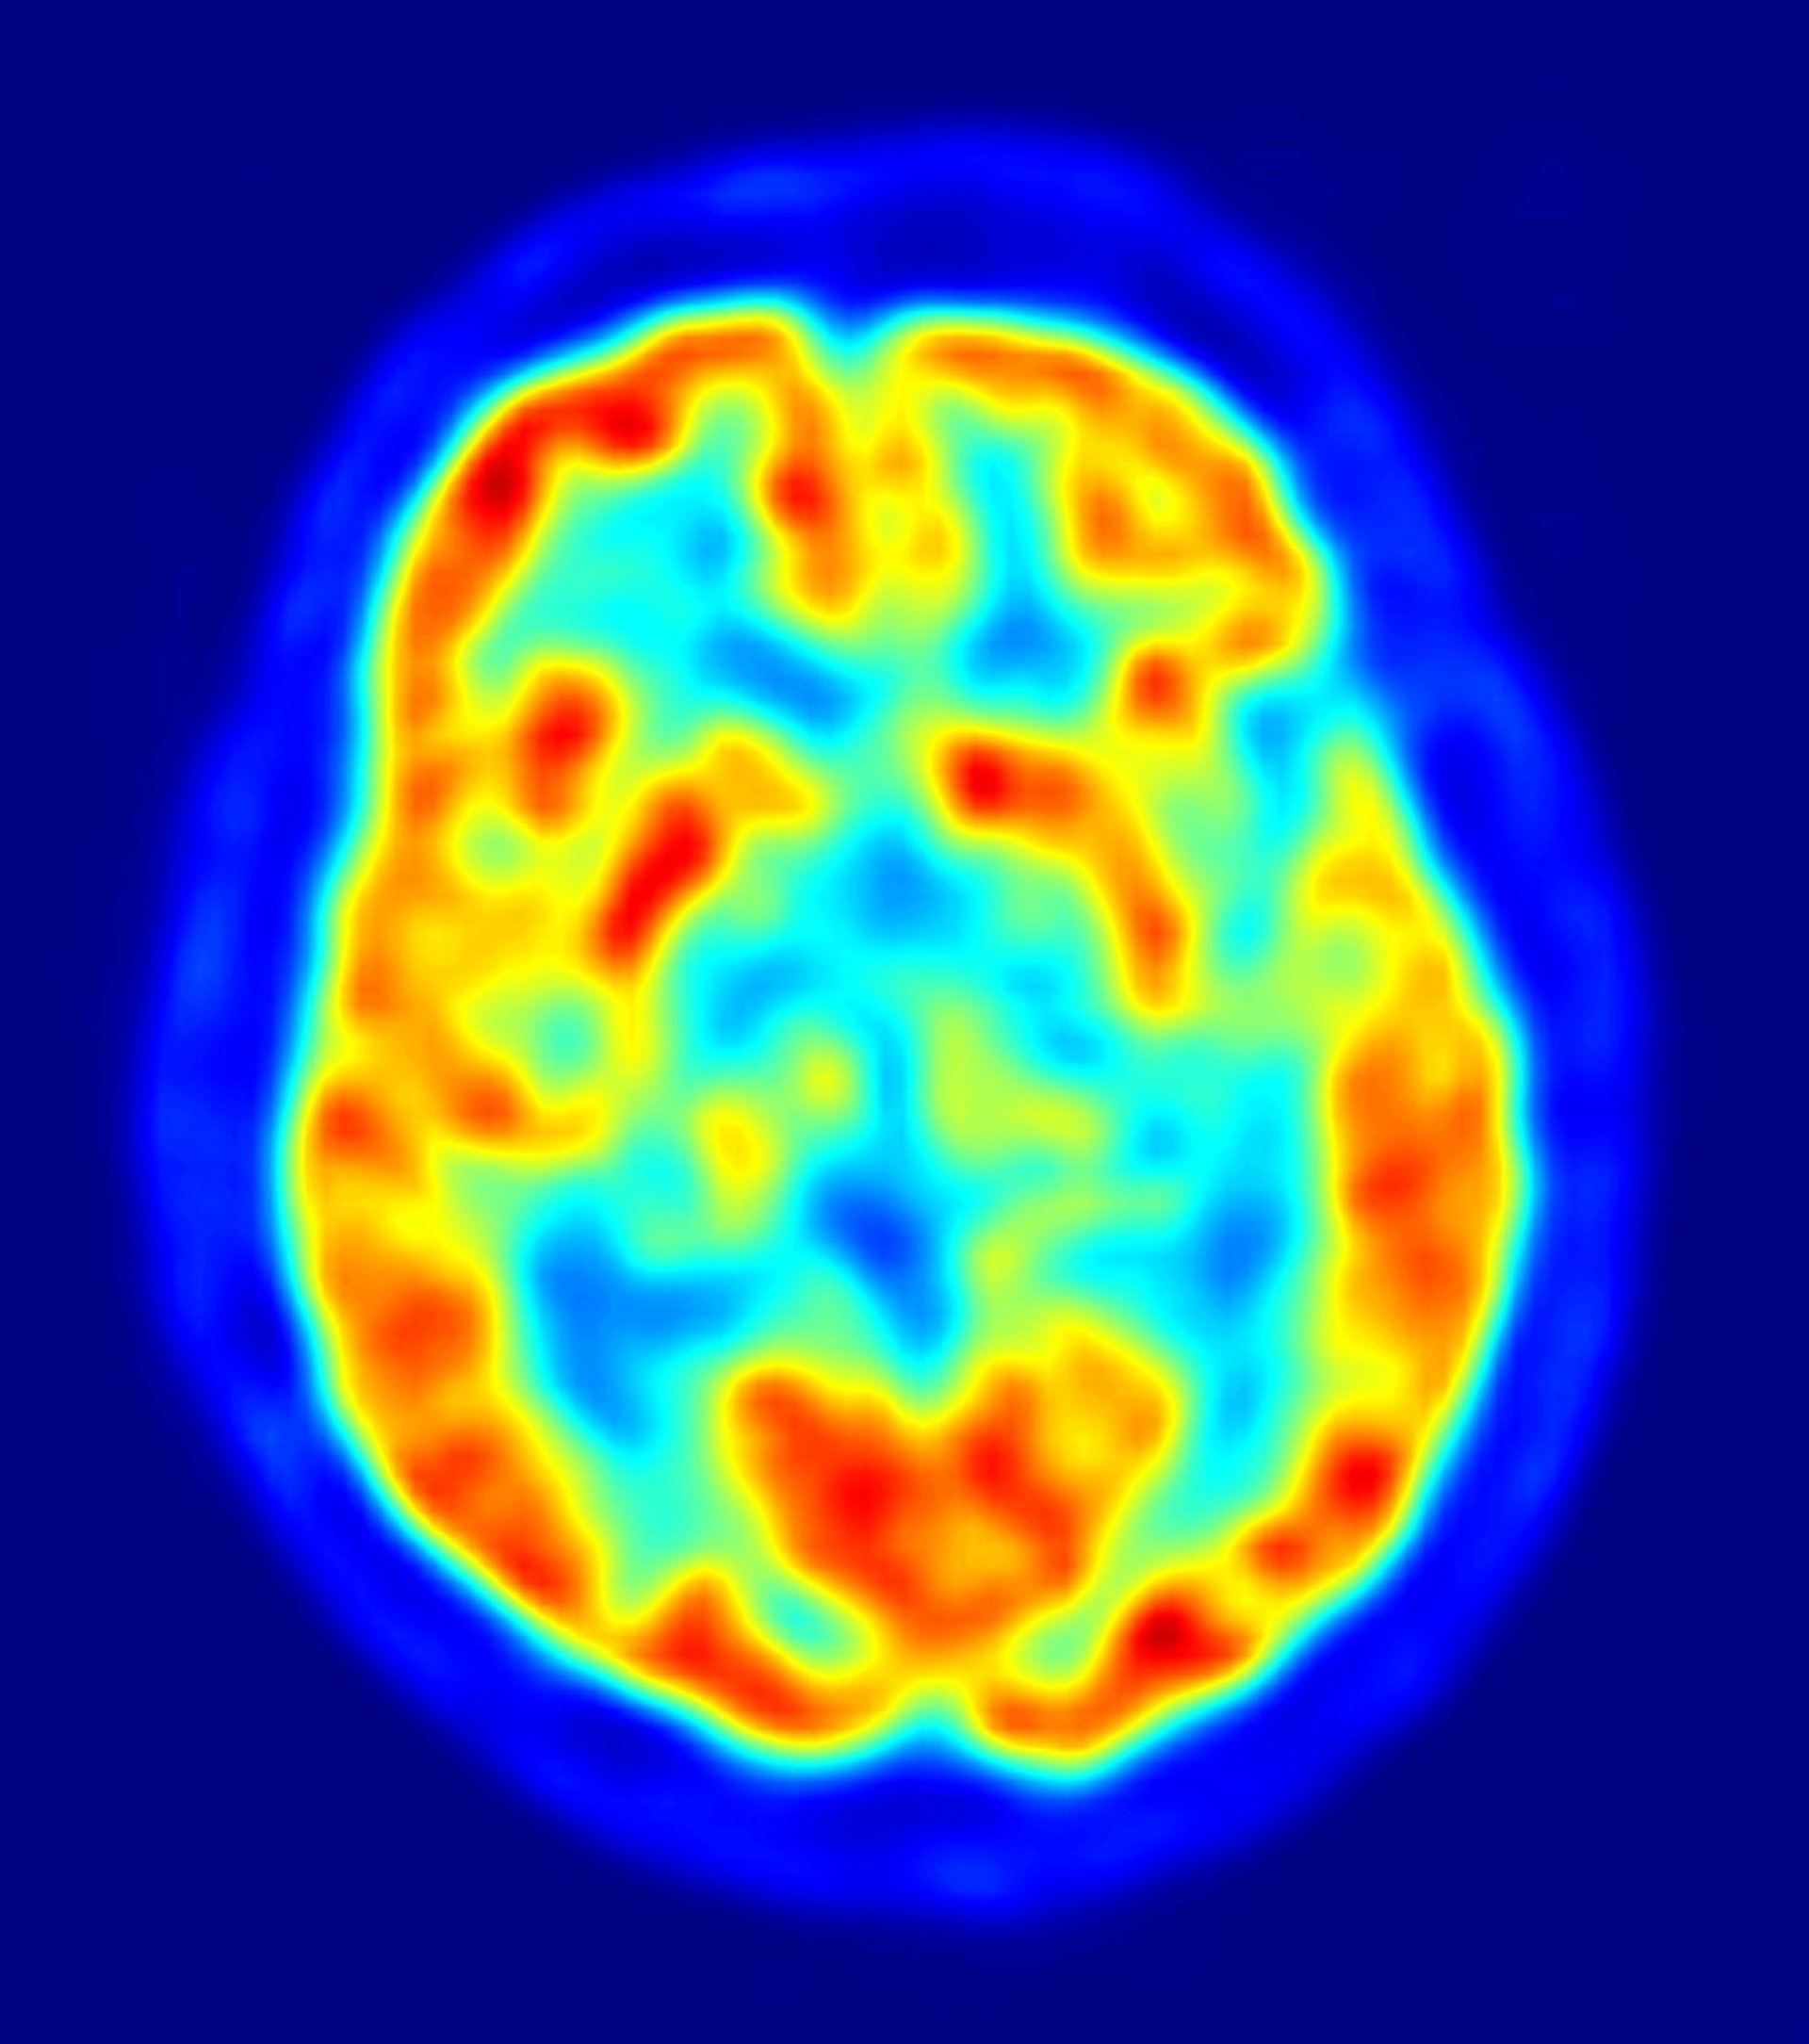

En el estudio participaron 121 personas mayores de 65 años de Chicago. Se midieron los niveles de vitamina B12 y B12 relacionados con los metabolitos que pueden indicar una deficiencia de vitamina B12. Los participantes también pasaron por pruebas de memoria y otras habilidades cognitivas. Un promedio de cuatro años y medio más tarde, imágenes por resonancia magnética de los cerebros de los participantes midieron el volumen cerebral total y otros signos de daño cerebral.

Tener niveles altos de cuatro de los cinco marcadores de deficiencia de vitamina B12 se asoció a menores puntuaciones en los tests cognitivos y a un menor volumen cerebral total.